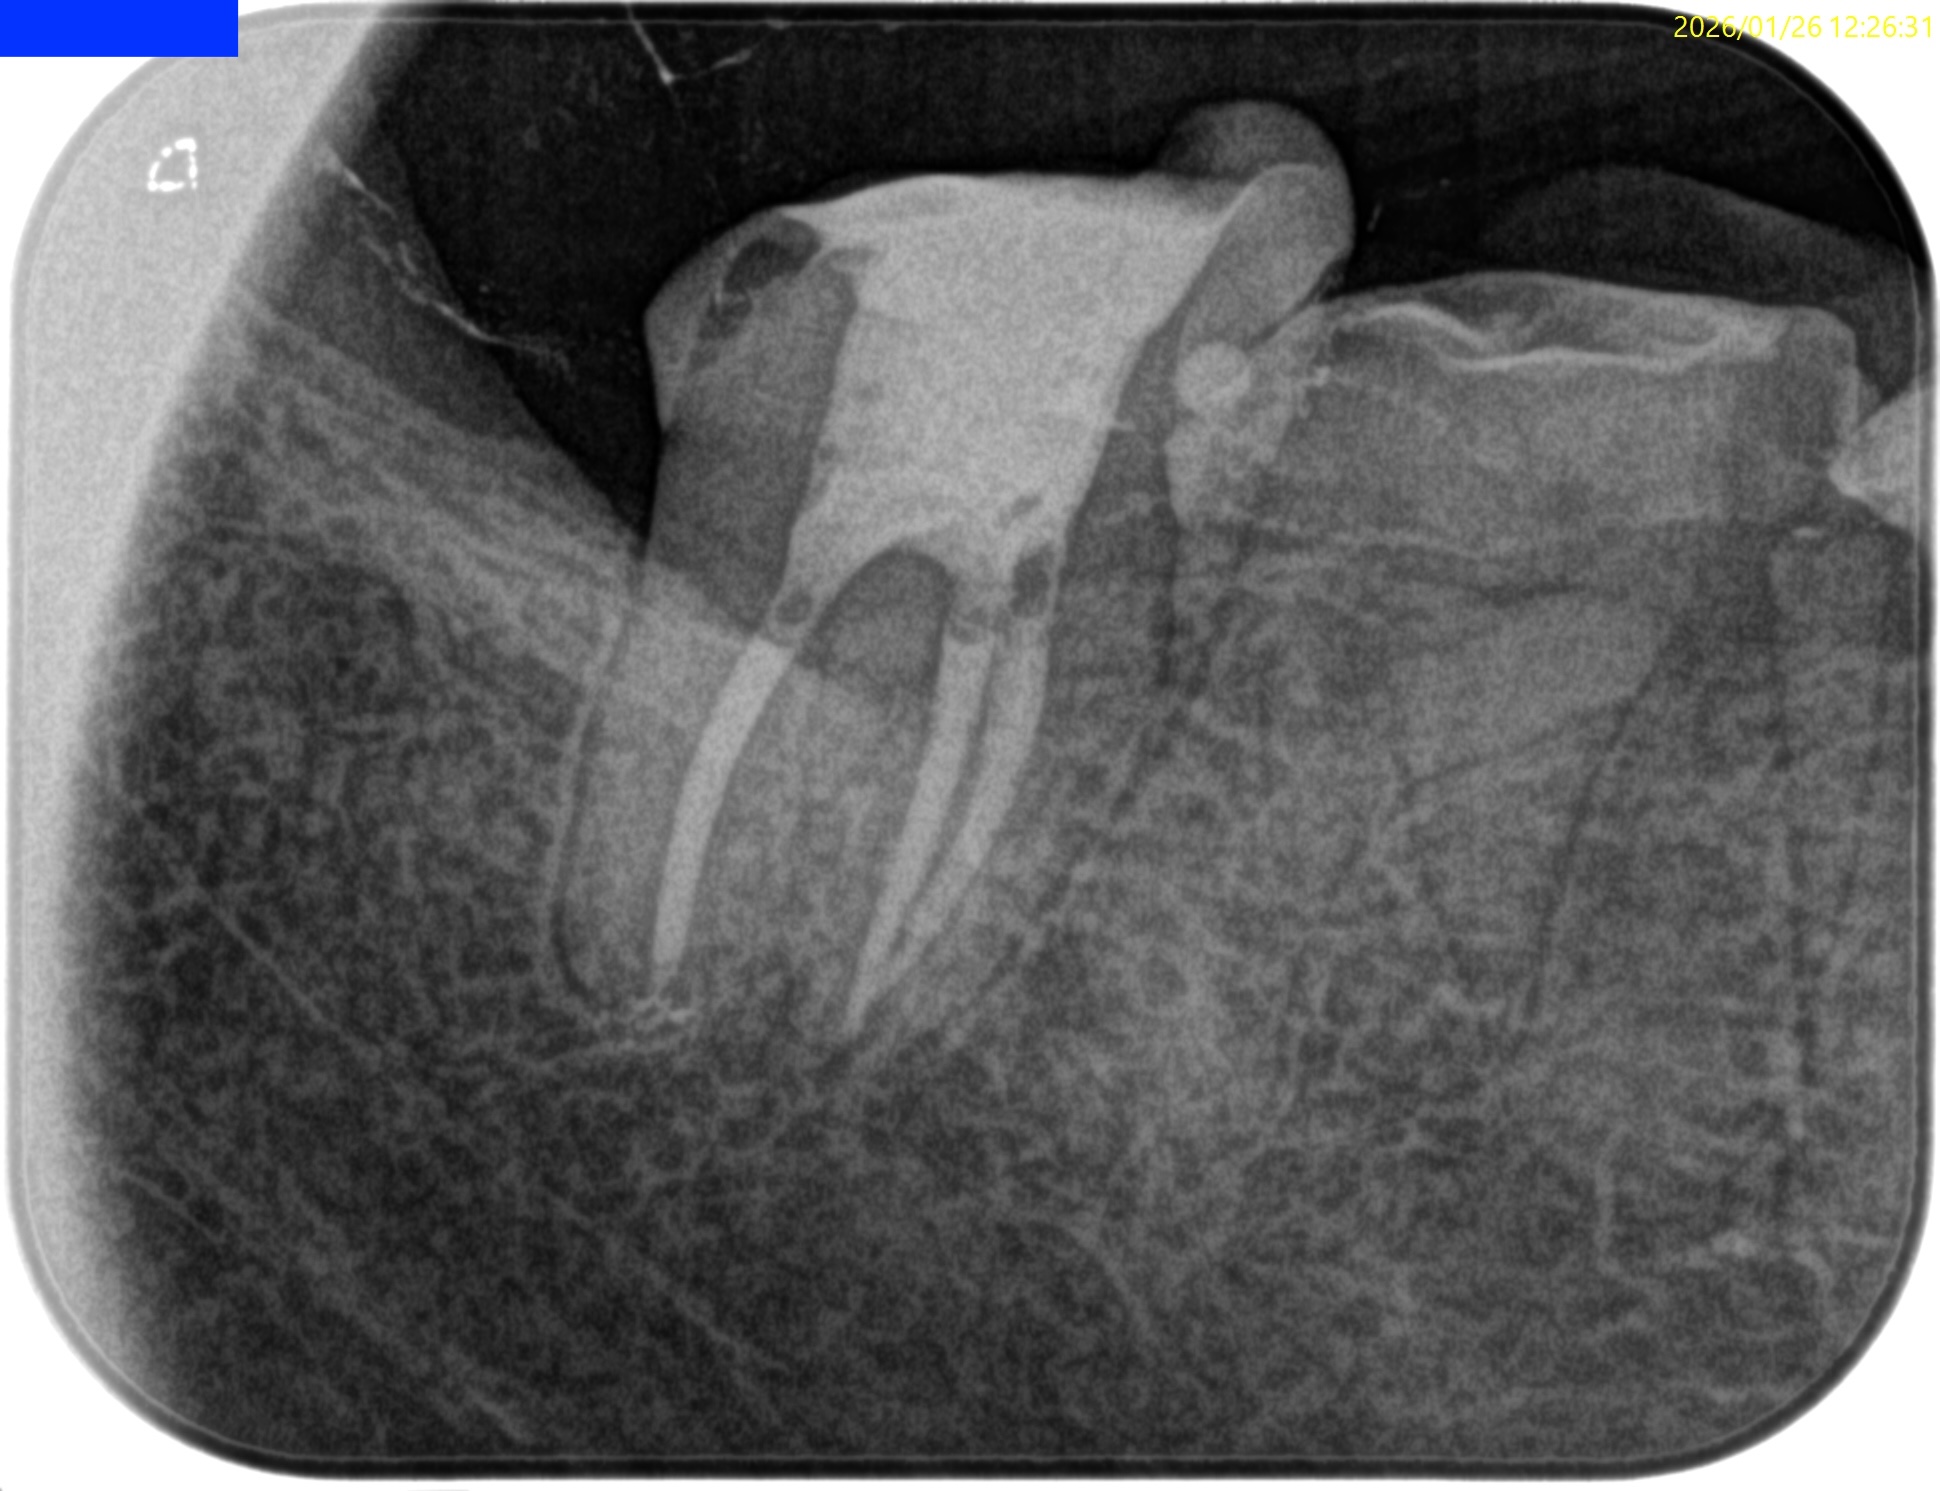

#31 Dに直覆したような痕跡がある。

遠心根管だが、

遠心舌側は既に露髄しているだろう。

MLとMBは合流根管であるので合流を確認した。

術後にPA, CBCTを撮影した。

MB

ML

D